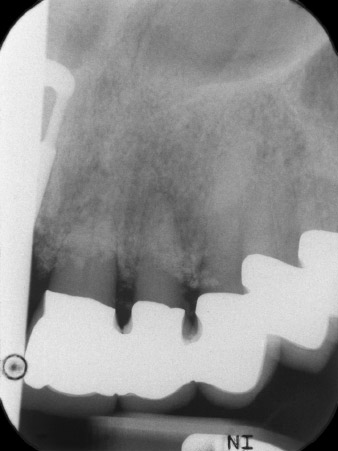

resultados radiológicos iniciales

Imagen. 1: Los resultados radiológicos iniciales mostraban una pieza con una corona bloqueada que debía reemplazarse. Durante la extracción, se extrajeron por accidente las piezas dentales 21 y 22.

En la primera visita se trataron las piezas 21, 22 y 23, que presentaban bloqueo en las coronas colocadas hacía 19 años. Estas estaban unidas mediante una férula con los implantes de las posiciones 12/11 (figura 2). La imagen radiológica muestra una pérdida ósea horizontal alrededor de las piezas dentales 21 y 22 (figura 1).